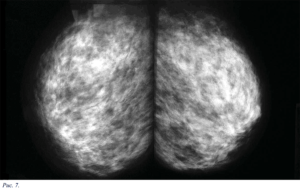

На рентгенограммах выявляют множественные тени неправильной фирмы с нечеткими, расплывчатыми контурами. Каждая тень соответствует участку лобулярной гиперплазии, совокупность теней образует неоднородную неравномерную тень, занимающую почти всю молочную железу.

Диффузная фиорозно-кистозная мастопатия с преобладанием фиброзного компонента.

Клиническая картина и субъективные ощущения почти такие же. как при форме мастопатии, описанной выше. Рентгенологическая картина обеих форм также сходна.

Вся молочная железа интенсивно затемнена, имеет узкую полоску просветления, образованную подкожно-жировой клетчаткой.

В отличие от аденоза, при фиброзе контуры отдельных участков лобулярной гиперплазии подчёркнуты, а не разрыхлены. Эта форма мастопатии встречается в 30,7% случаев.

Диффузная фиброзно-кистозная мастопатия с преобладанием кистозного компонента.

Встречается у 17,4% всех женщин с мастопатией. При морфологическом обследовании обнаруживают множественные кисты, расширение протоков, преобладание фиброза, атрофию долек.

Клиническая картина такая же, как у предыдущих форм мастопатии, но, в отличие от них, могут пальпироваться отдельные уплотнения округлой или овальной формы, эластической консистенции, отграниченные от окружающих тканей, если их размер превышает 2 см.

Более мелкие уплотнения при пальпации не всегда обнаруживают вследствие мягкой консистенции, в этом случае помогает рентгенография.

На рентгенограммах на фоне пёстрого неоднородного рисунка, обусловленного чередованием жировой, соединительной и железистой ткани, видны уплотнения — округлые, овальные или с вдавлениями от соседних кист.

Размеры уплотнений колеблются от 0,3 до 6-8 см, их контуры чёткие, ровные, с ободком просветления, свидетельствующим об экспансивном росте. При наличии в кистах нескольких камер их контуры полицикличные, резкие. Наиболее информативный метод диагностики — УЗИ.

Смешанная форма диффузной фиброзно-кистозной мастопатии.

Встречается в 38,6% случаев. Морфологическая картина довольно пёстрая: избыточное развитие железистых долек, склерозирование внутридольковой и междольковой соединительной ткани, превращение альвеол в микрокисты.

Различают непролиферирующую и пролиферирующую формы мастопатии; на фоне последней рак встречается в 7-14 раз чаще. Клинически заболевание проявляется ощущением болей различной степени выраженности, даже при прикосновении одежды. При пальпации выявляют либо диффузную мелкую зернистость, либо дисковидную тестоватость.

В рентгенологическом изображении отмечается нарушение нормального структурного рисунка, выражающееся в чередовании просветлений и затемнений округлой, овальной или неправильной формы, сочетающихся с хаотически расположенными плотными фиброзными тяжами. Нередко УЗИ вносит ясность, уточняя, какие структуры преобладают.